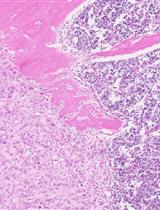

One month after surgery, tumors can be harvested to measure tumor weights and tumor volumes. However, the tumor growth rate and tumor volumes depend on the cell lines that are injected. Tumor diameters are measured by a digital caliper, and the tumor volume (mm3) is calculated by the formula: Volume = (width)2 x length/2. Tumors can be further confirmed by immunohistochemical staining for Ki67/haematoxylin after resection. In addition, depends on availability of equipment and reagents, small animal imaging instrumentations, including x-ray computed tomography (CT), magnetic resonance imaging (MRI) or bioluminescence imaging, are useful tools to non-invasively measure burden of xenografted tumors. Lymph node, liver, and lung metastases can be further examined by bioluminescence imaging (if cells contain luciferase) or by microscopic analysis after Ki67/haematoxylin staining within 16 weeks after injection. At least five mice are recommended for each group. A P value < 0.05 is considered as significant using Student’s t-test. However, the number of mice to be used depends on the hypothesis tested and on the statistical test. A power analysis should be done prior to the start of the experiment.